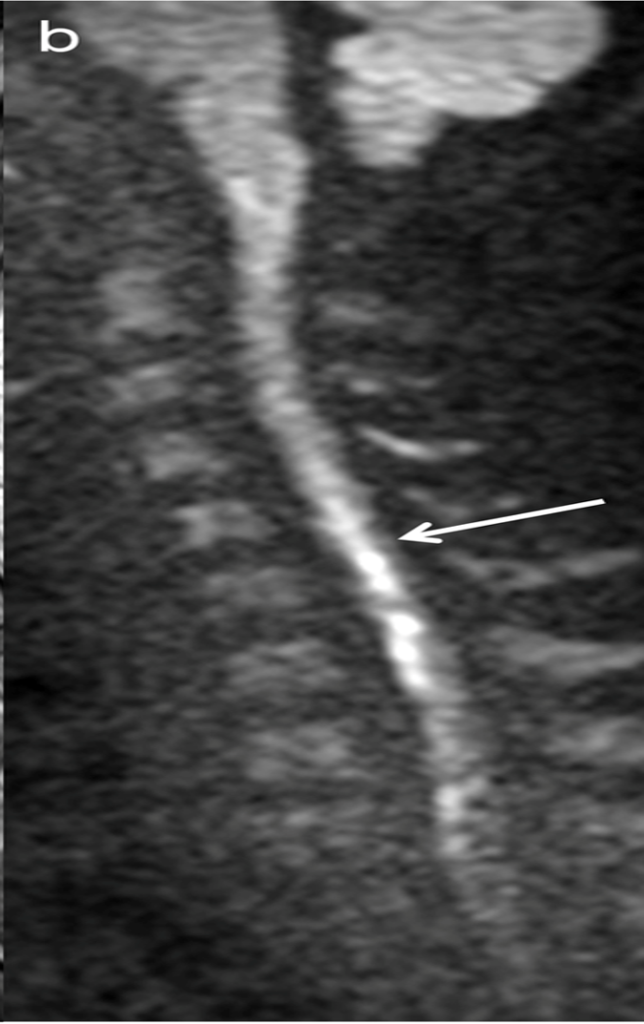

• 52-year-old man with subacute combined degeneration of spinal cord. Sagittal T2-weighted MR image shows abnormally increased signal intensity (arrows) along posterior columns of spinal cord extending from C1 through C6.

• Follow-up sagittal T2-weighted MR image obtained 3 months after A and B shows near total resolution of signal abnormality.